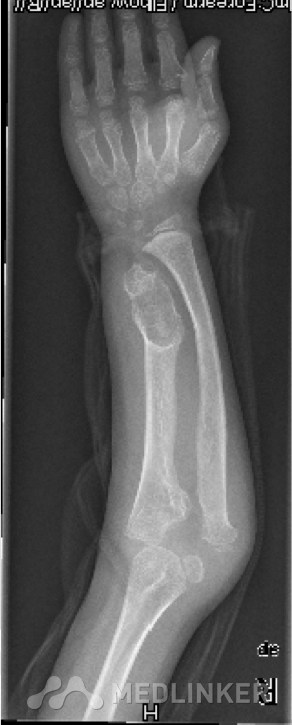

先天性骨软骨瘤病伴桡骨头脱位

桡骨头脱位

大家讨论一下这个小孩的矫形方法!